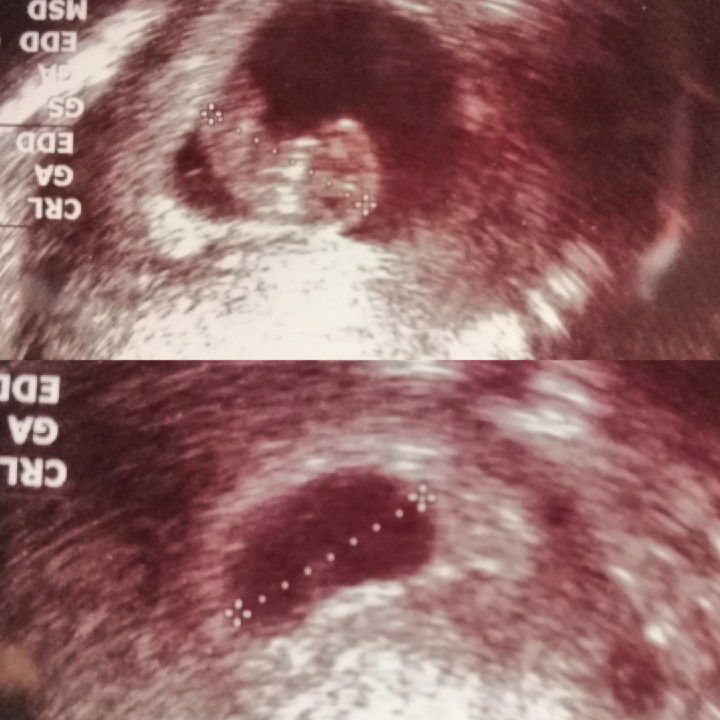

คราบน้ำตาล

11 w +1d. วันจันทร์และอังคาร น่าจะเดินมาก มีคราบสีน้ำตาลติดมากีบผ้าอนามัยอีกแล้วค่ะ ปกติผ้าอนามัยจะสะอาดเป็นสีขาว เช้าวันพุธมีคราบสีน้ำตาลติดกางเกงใน.... โทรหาหมอ หมอก็บอกให้อยู่นิ่งๆ พักมากๆ ตอนนี้กลัวไปหมดค่ะ

ฝ่อ

ก็ยังคิดอยู่นะว่าให้เขายังอยู่.... แต่ยังไม่ได้ยินเสียงหัวใจอีกดวง... ได้ยินแค่ดวงเดียว